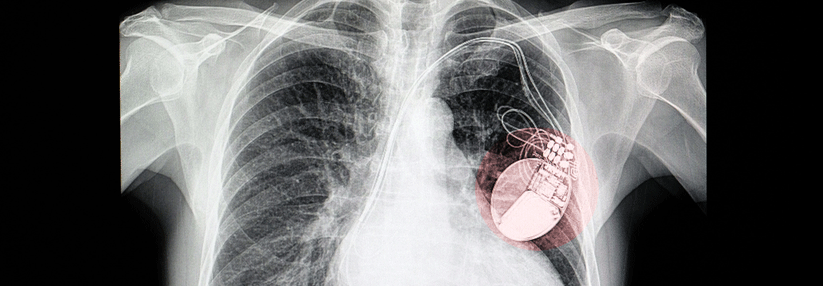

Für wen kommt ein Herzschrittmacher infrage? Für wen kommt ein Herzschrittmacher infrage? © iStock.com/Jan-Otto

Implantationen von Herzschrittmachern und Kardioverter-Defibrillatoren zählen zu den häufigsten Operationen in Deutschland. Mehr als 100 000 wurden im Jahr 2016 durchgeführt. Die Indikationen sind relativ eng gefasst, denn nicht jeder profitiert von den Geräten.